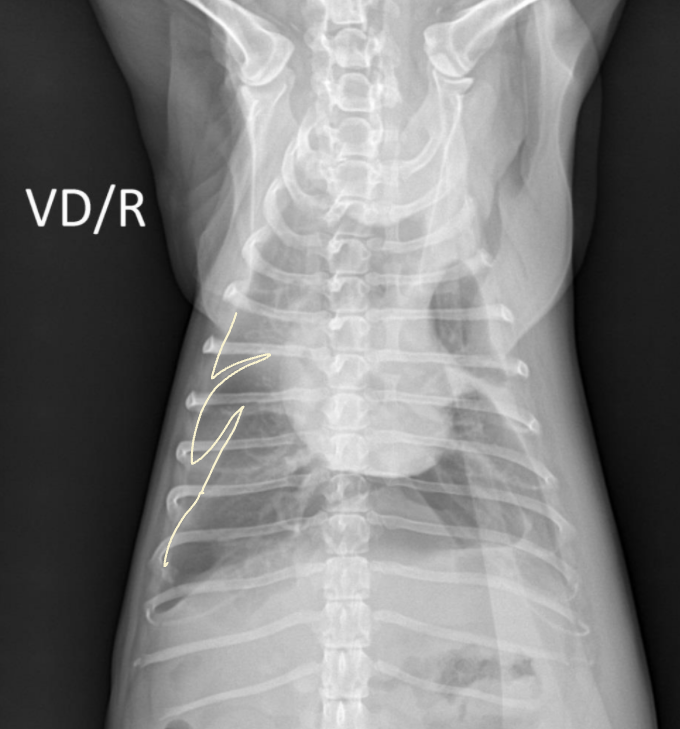

| Radiographic signs interlobar fissure ๋๊ป๊ฒ ๊ด์ฐฐ๋๊ณ , ํ๋ฒฝ์ด ๋จ์ด์ ธ ๋๊ฐ ๊ฒ์ฒ๋ผ ๋ณด์ | Radiographic signs ์ฌ์ฅ์ด ๋ ์๊ณ , ํ๊ฐ ์ชผ๊ทธ๋ผ๋ฆ | |

| - Interlobar fissure widening - Lung retraction - Pleural wall thickening - Scallop sign - Cardiac effacement - Blunt angle | - Retraction of pleural surface - Collapsed lung (โ opacity ์ฆ๊ฐ) | |

![]() | ![]() | |

![]() ![]() | ![]() ![]() | |

![]() |